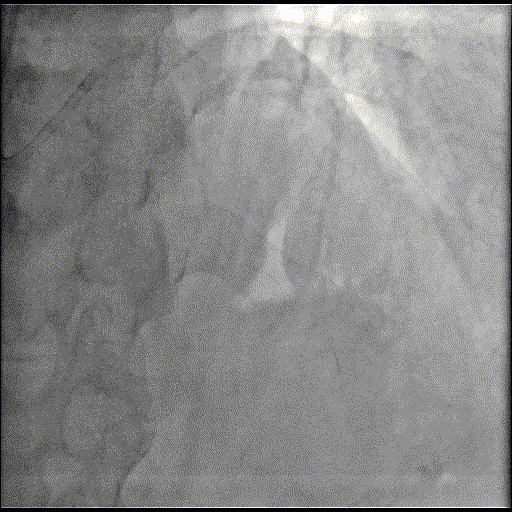

基础造影

右冠状动脉近中段可见支架影,支架通畅无狭窄,右冠状动脉远段狭窄50%;前降支近中段弥漫性重度钙化伴成角,近段狭窄80%,中段狭窄90%,第一对角支近段狭窄70%;回旋支近段狭窄70%,第一钝缘支狭窄90%。

手术经过

OM优先处理:

球囊预扩

用预扩张球囊对OM病变部位行预扩张。

支架植入并后扩

于LCX中段至OM支植入一枚药物洗脱支架,经非顺应性球囊后扩张支架,复查造影提示支架贴壁良好,无夹层撕裂。

LAD处理:

用预扩球囊扩张LAD病变,支架无法通过。为了解血管病变分布情况及钙化程度,遂启用IVUS检查。

术前腔内影像学IVUS指导

IVUS提示LAD近中段钙化病变,中段可见360°环形钙化。

冲击波球囊治疗

3.0x12@4atm 冠脉血管内冲击波导管顺利推送至前降支近端,但无法通过成角钙化处,故于血管近端就地进行10个周期治疗,复查造影见近端狭窄明显减轻;再次选择2.5x12@4atm冠脉血管内冲击波导管推送至成角钙化处,逐步掘进扩张病变并给予冲击波治疗,最终顺利通过成角钙化处,并于前降支中段再次进行10个周期的冲击波治疗。

于LAD近中段串联植入两枚药物洗脱支架,经非顺应性球囊后扩张支架,复查造影及IVUS提示支架膨胀完全,贴壁良好,无夹层撕裂。

LCX处理:

于LCX近段与原支架串联植人一枚药物洗脱支架,经非顺应性球囊后扩张支架,复查造影&IVUS提示支架贴壁良好,无夹层撕裂。

最终,经FFR检测,结果达0.96,提示冠状动脉功能学恢复满意,达到预期治疗目标,故本次介入治疗操作圆满结束。